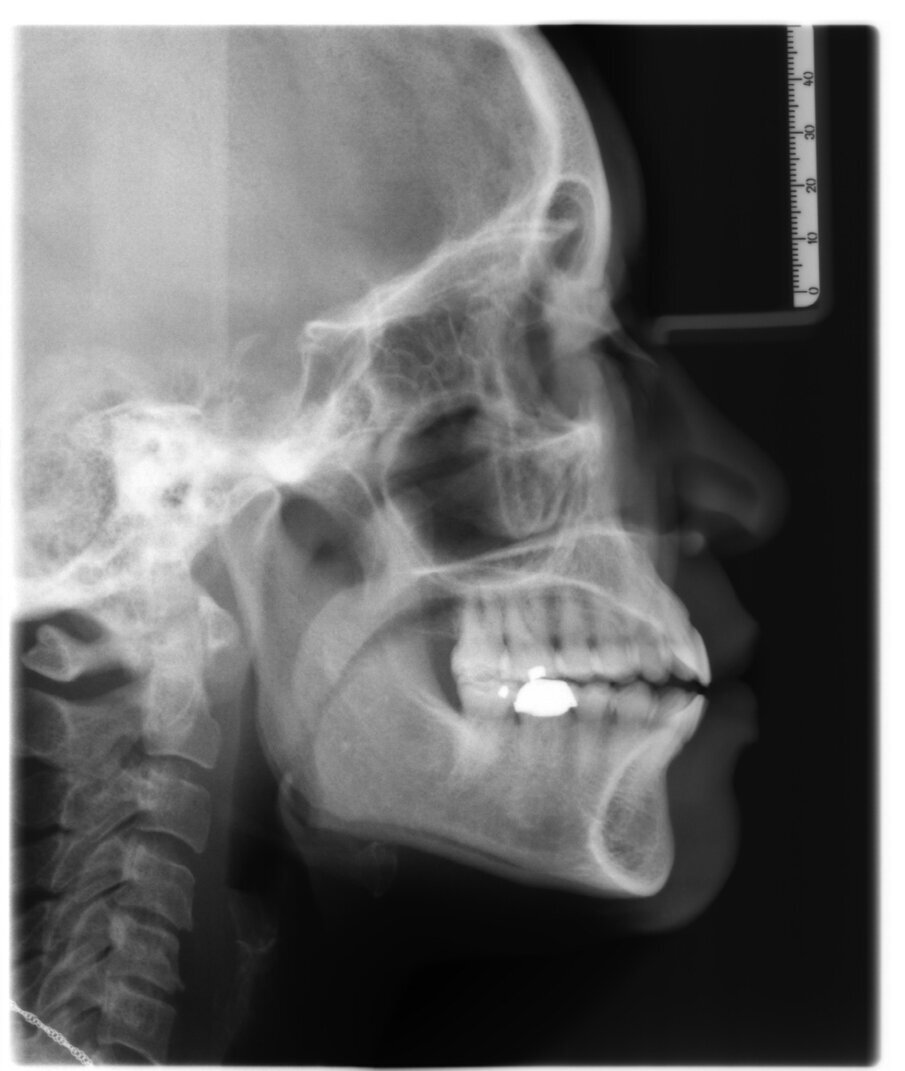

A 56-year-old female patient presented with a Class III malocclusion, anterior crowding and a 2-3 mm anterior open bite. Clinical photographs showed an ideal incisor display upon smiling. The panoramic film was unremarkable, and the lateral cephalometric film revealed a negative 1 mm overjet. (Figs. 1 to 10)